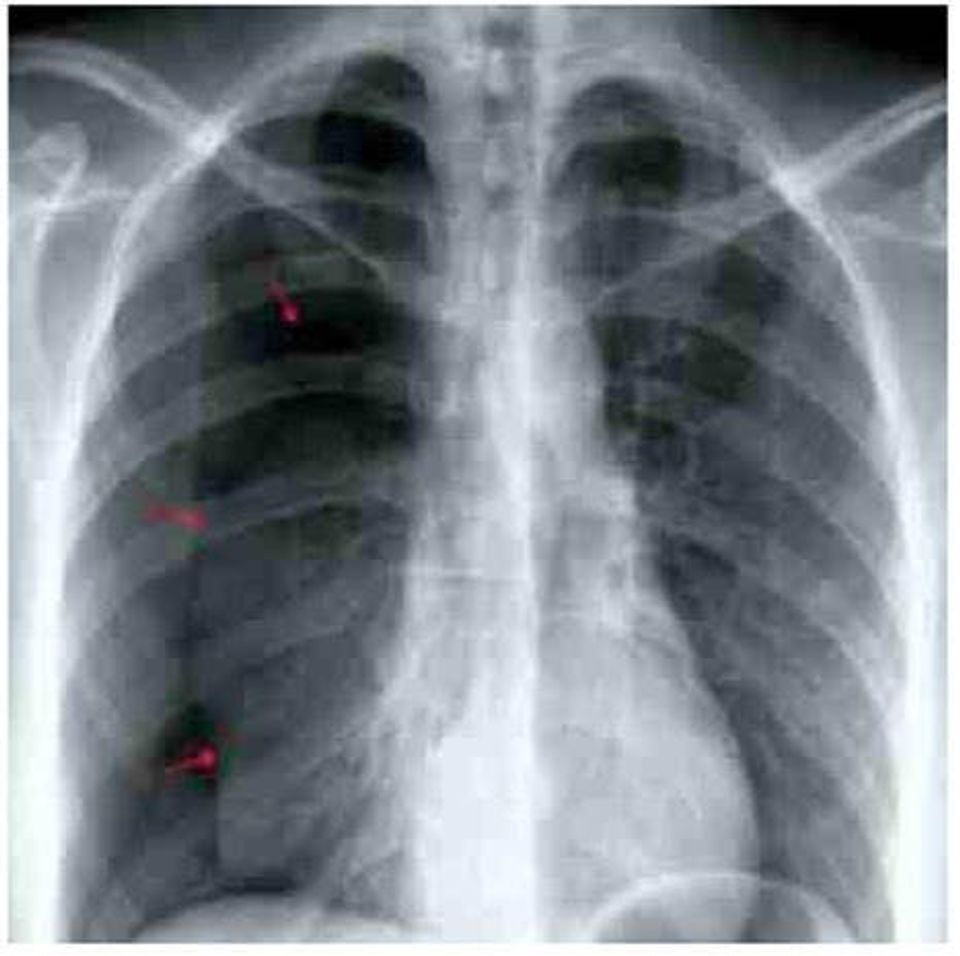

แอดมินเพจ Tensia ระบุด้วยว่า ผู้ป่วยเคสนี้ มีอาการปวดประจำเดือนและปวดระหว่างมีเพศสัมพันธ์มาตั้งแต่อายุ 20 ปี ช่วงใกล้ ๆ นี้เคยปอดขวาทะลุมาแล้ว 3 รอบ และมักจะเป็นช่วงที่มีประจำเดือน ซึ่งแค่พักก็หายได้เอง แต่รอบนี้มาด้วยเหนื่อยและเจ็บอกขวาขึ้นมาทันทีทันใด ออกแรงหรือหายใจเข้าแล้วเจ็บมากขึ้น ผลเอกซเรย์ พบปอดขวาแฟบลง (ลูกศรสีแดงคือแนวขอบของปอดที่หดลงมา) บ่งบอกว่ามีภาวะปอดทะลุ เกิดทางเชื่อมระหว่างโพรงอากาศในปอด กับช่องเยื่อหุ้มปอด ลมได้เข้าไปยังช่องเยื่อหุ้มปอด ทำให้ปอดสูญเสียในการสร้างความดันในขยายปอด